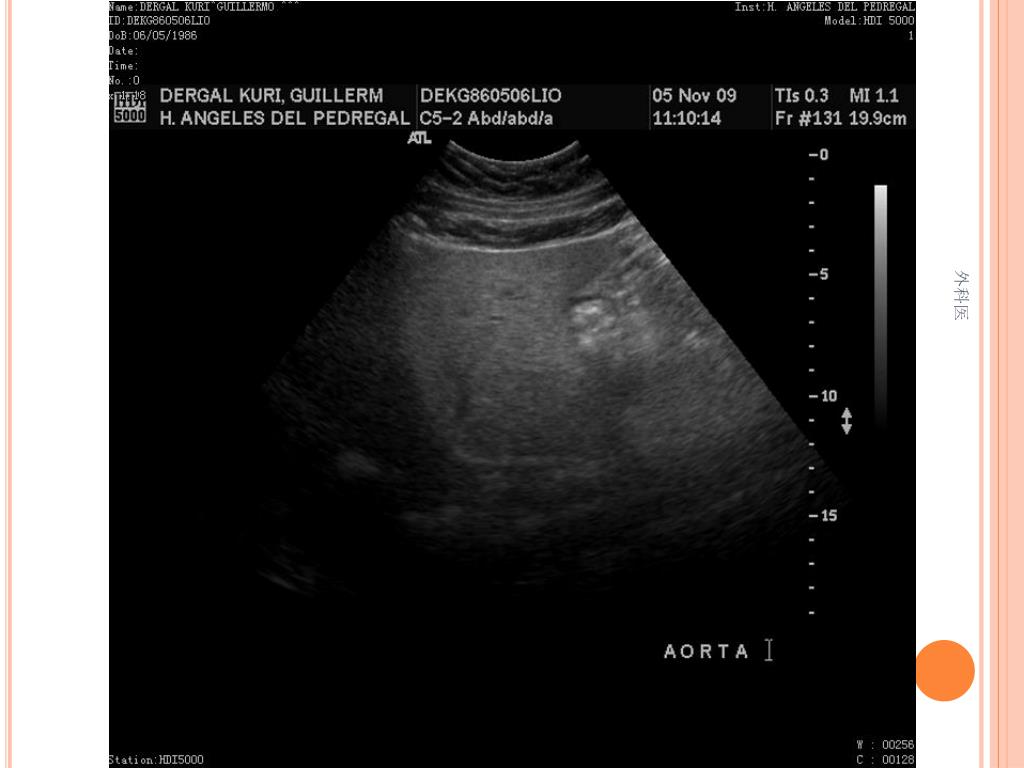

21. 外科医

44. Tips • Leucocitos Mas de 20000/ml • Mas de 20% de la apéndices no se llenan con el bario por enema. • USG sensibilidad del 85% y Especificidad de mas 90% para Apendicitis Aguda. • TAC de Abdomen cortes de 5mm, sensibilidad y especificidad del 90% para dolor abdominal. • Analisis de 75000, taza de apendice negativa de 6% Hombres y 13% Mujeres 外科医